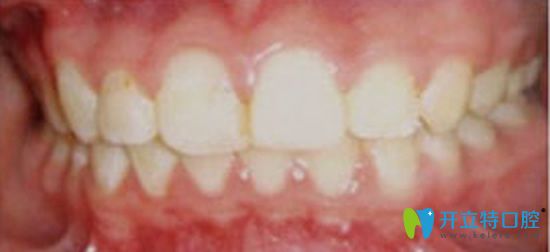

看看孩子牙齒矯正一年后的效果好不好:

太平洋口腔牙齒矯正一年后的效果

劉正秋醫(yī)生不辭辛苦的為孩子的矯治器做了數(shù)次的調(diào)整,一年后的效果很不錯(cuò),隱形無托槽矯正,讓我的孩子擁有了一口健康整齊的牙齒。